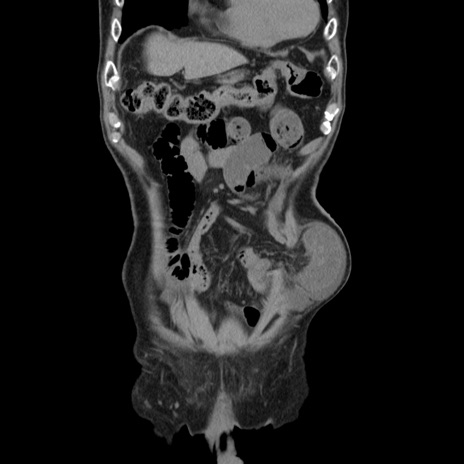

症例24(冠状断像)

【症例】80歳代男性

【主訴】左側腹部痛、嘔吐

【現病歴】本日早朝より左腹部に痛みあり。昼頃嘔吐認めたため、救急要請。

【既往歴】直腸癌(Mile手術)、胆摘

【身体所見】意識清明、BT 35.9℃、BP 221/93mmHg、SpO2 97%(RA) 、腹部:左ストーマ周囲に限局性の腹部膨隆あり。 膨隆部自発痛・圧痛あり・軟。

【データ】WBC 7700、CRP 0.09